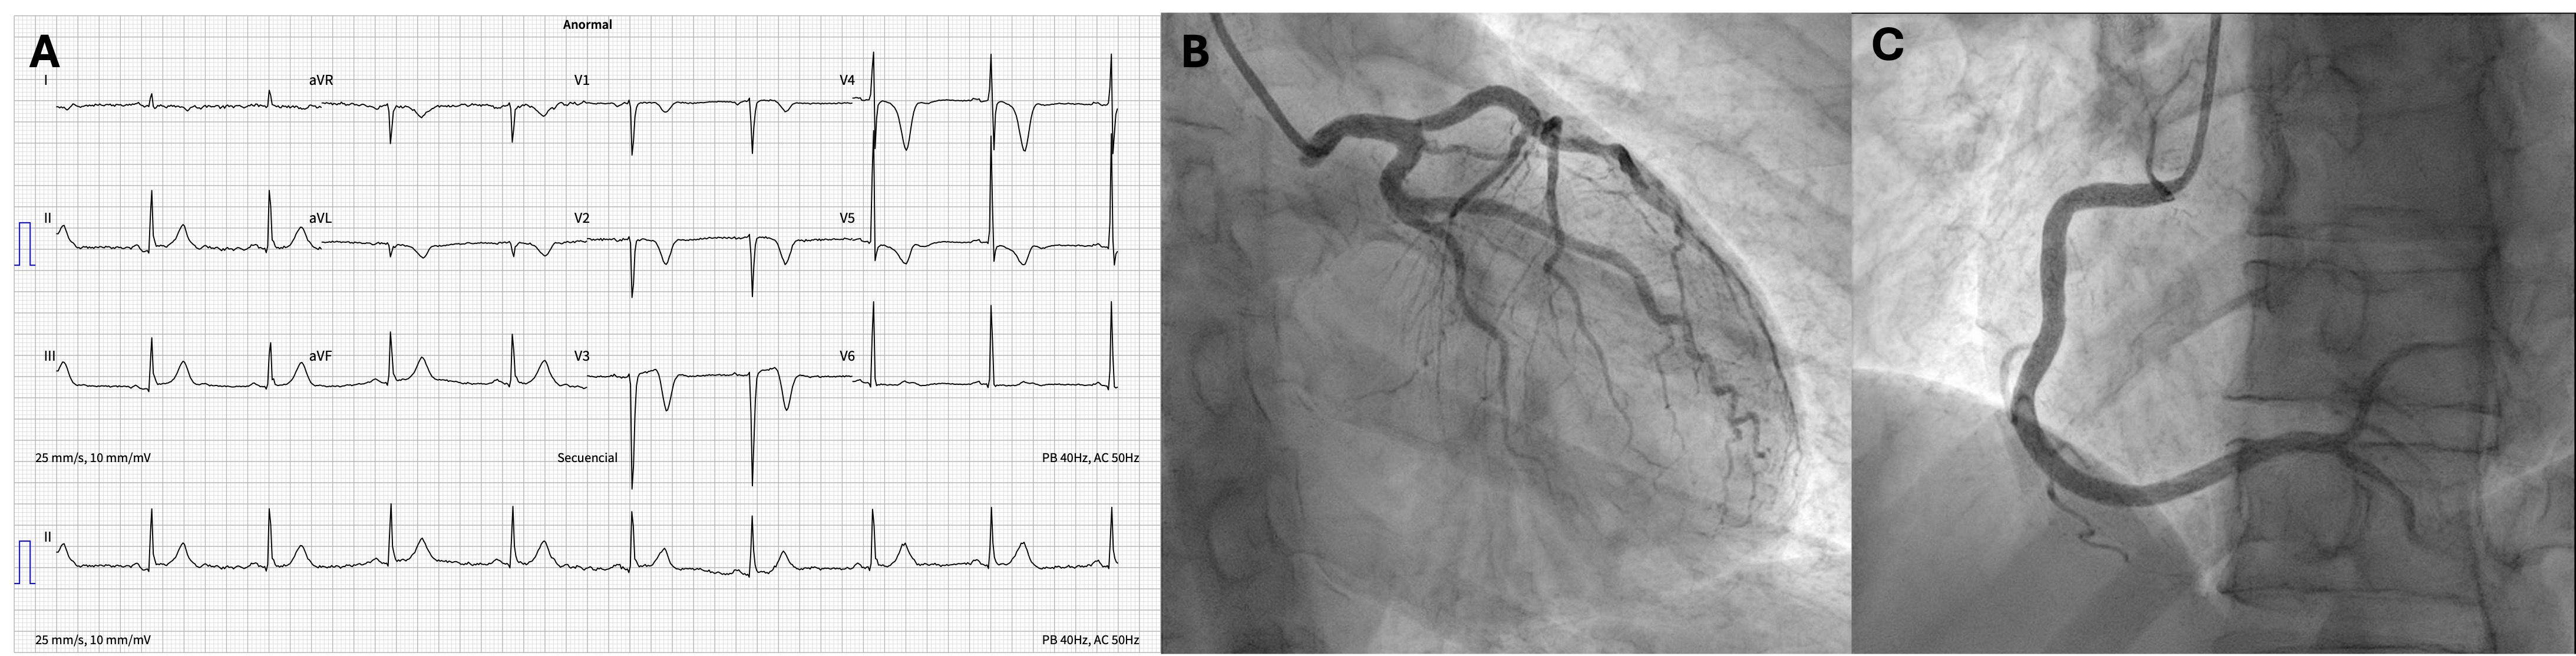

A: SSFP sequence, 3 chamber view showed anterior septal hypokinesia. B and C: elevated T1 and T2 mapping values consistent with edema. D: LGE in the apicoseptal segment, findings compatible with acute myocardial infarction in the LAD territory